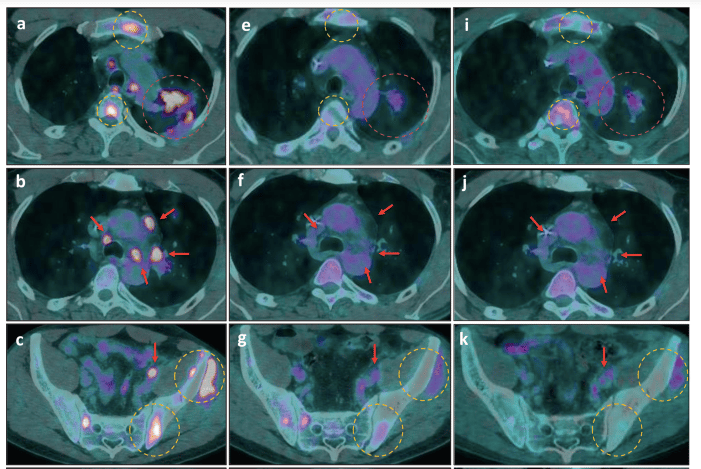

After revisiting his previous NGS report (and considering the patient´s good performance status), we prescribed dabrafenib 75mg bid, trametinib 1mg OD and osimertinib 80mg OD. He experienced remarkable pain relief within 2 weeks of treatment, with only mild treatment-related toxicities. His radiological response in the first follow-up PET-CT was impressive, with nearly 70% tumor burden reduction as assessed by PERCIST criteria (Figure 2 - panels e, f, and g). He remained progression-free until October when mild progression occurred. Throughout his entire treatment, longitudinal ddPCR ctDNA assessment demonstrated its interesting and useful concordance with PET-CT scan, which underscores this methodology´s potential to anticipate imaging findings.